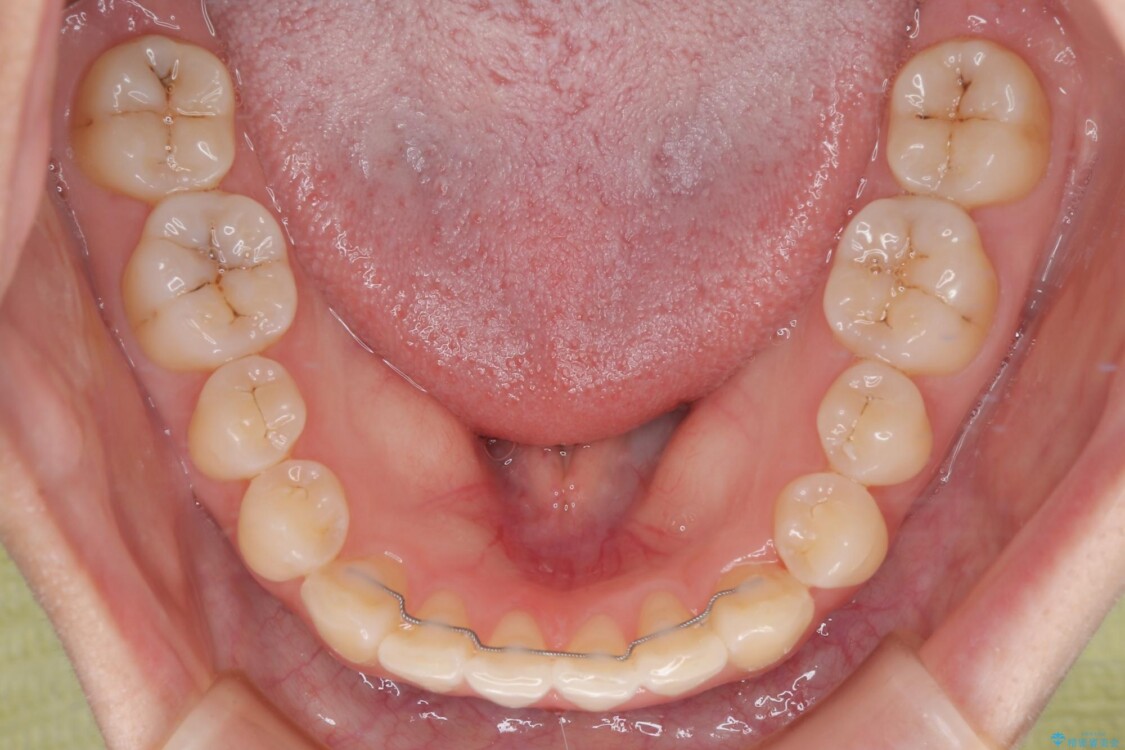

診察の結果、上下の前歯部に**叢生(そうせい/歯のガタガタ・重なり)**が認められました。

特に上の前歯にはねじれや重なりがあり、審美的にも清掃性にも影響している状態でした。

また、上顎前歯の重なっていた部分にはむし歯が見つかり、治療中に適切な処置を行っています。

治療前

• 前歯のねじれ・ガタガタを10か月で改善!20代女性の矯正治療|クリアブラケットでむし歯になりにくい歯並びへ改善 治療前画像